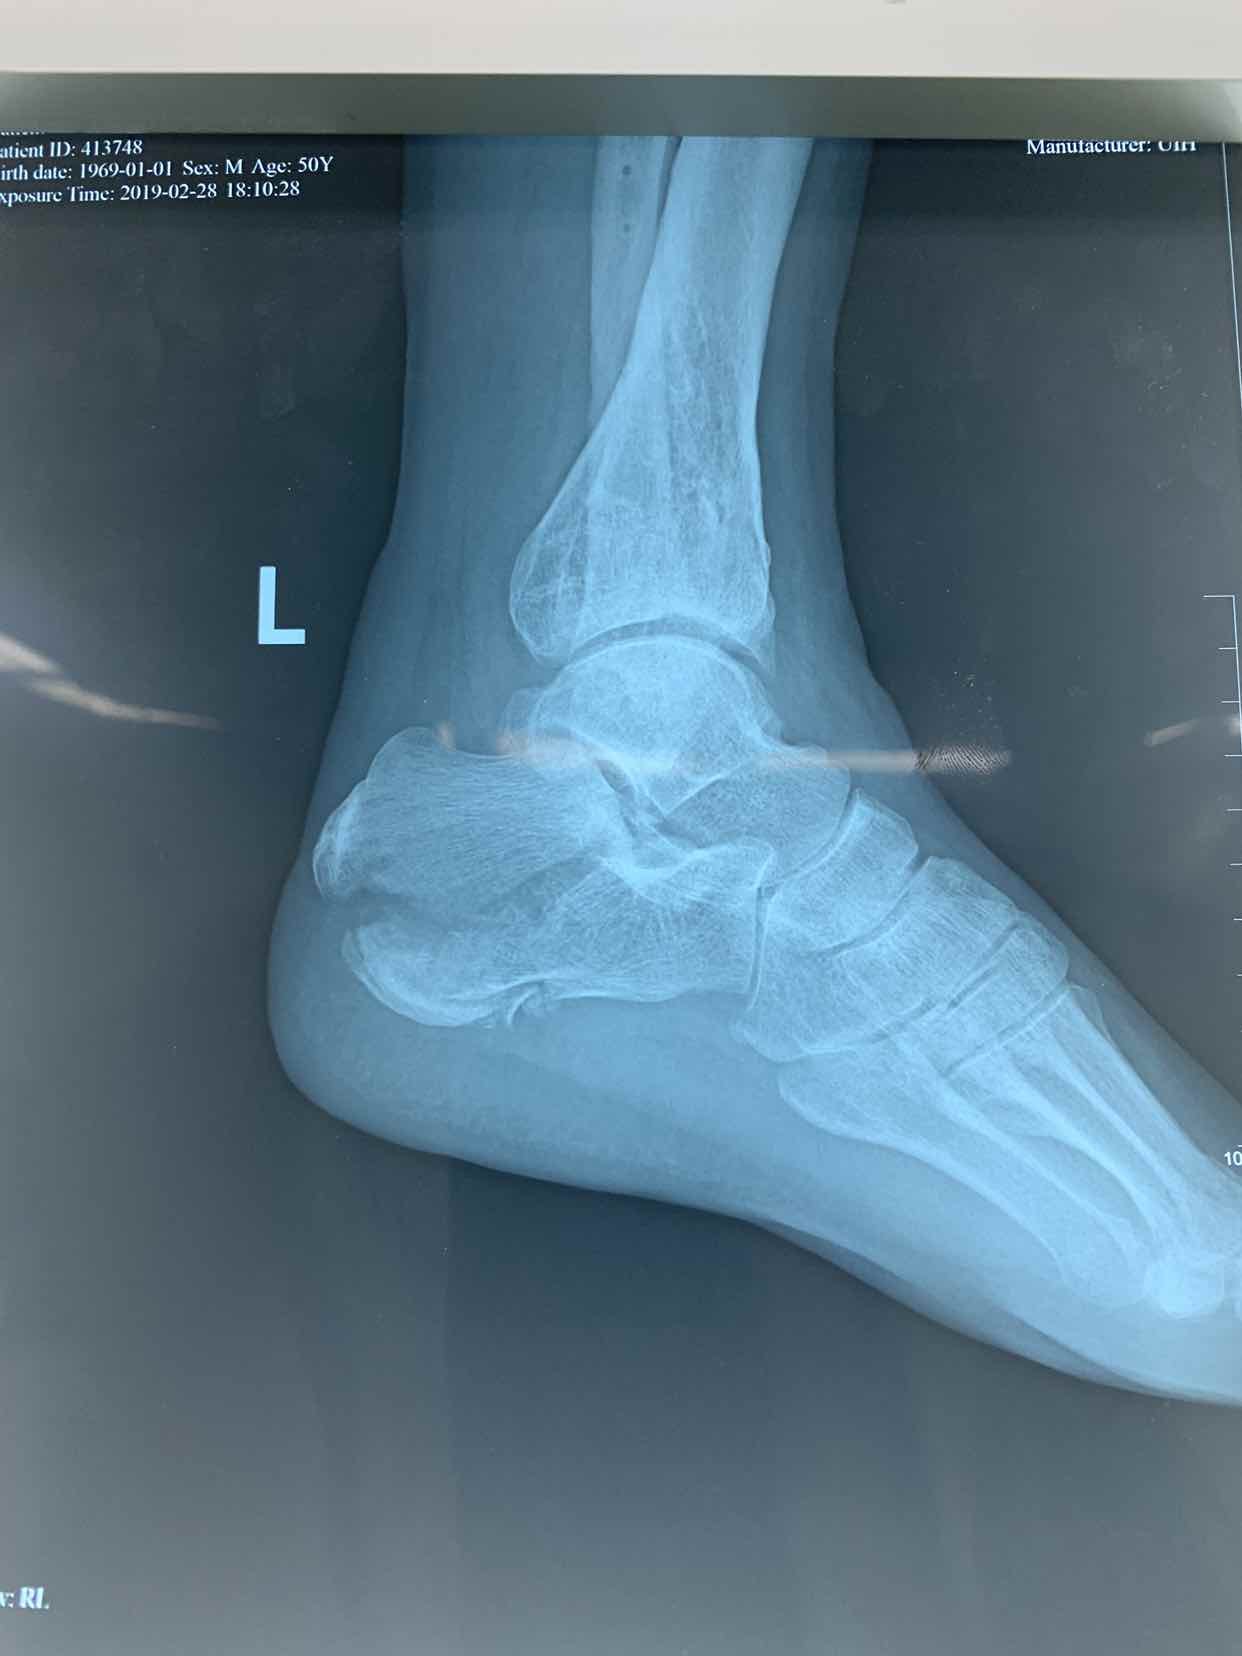

患者因自二米高处坠落,左侧足跟肿痛畸形活动受限一小时收入院。患者于一小时前不慎自二米高处坠落。当即左侧足跟肿痛。畸形。不能下地走路。急来诊。门诊拍片提示左侧跟骨骨折。门诊以左侧跟骨骨折收入院。

查体见左侧左跟局部肿胀。足弓消失。跟骨横径增宽。局部畸形。活动受限。不能下地走路。局部皮下淤血。拍片提示左侧跟骨粉碎性骨折。断端移位。